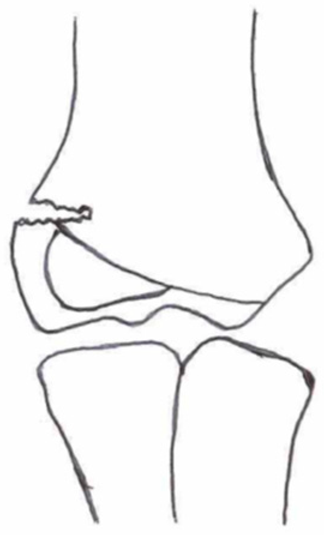

2.3. Classification of Fractures

| Classification | Type 1 (A) | Type 2 (B) | Type 3 (C) | Type 4 | Type 5 |

|---|---|---|---|---|---|

| Milch. [16] | ![]() | ![]() | |||

| Jacobs et al. [21] | ![]() | ![]() | ![]() | ||

| Finnbogason et al. [22] | ![]() | ![]() | ![]() | ||

| Weiss et al. [23] | ![]() | ![]() | ![]() | ||

| Song et al. [4] | ![]() | ![]() | ![]() | ![]() | ![]() |